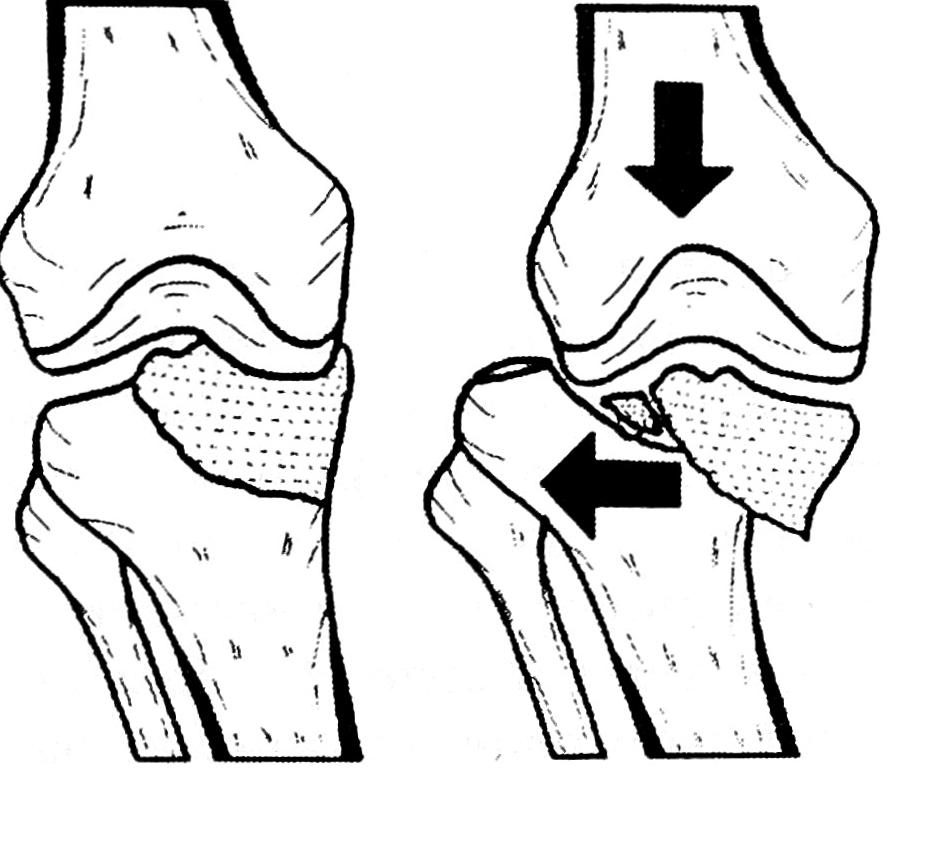

В тех случаях, когда с помощью скелетного вытяжения устранить смещение отломков и подвывих или вывих голени не удается, в клинике применяется закрытая репозиция отломков, устранение подвывиха или вывиха голени с фиксацией фрагментов болтом-стяжкой. Операция выполняется на ортопедическом столе под контролем рентгеновского аппарата с электронно-оптическим преобразователем. Винтовыми устройствами осуществляется тяга по длине с противоупором в промежность. В подколенную область помещают подставку-валик. После устранения смещения отломков и восстановления суставной щели делают два разреза кожи и мягких тканей в области латерального и медиального мыщелков большеберцовой кости длиной 1,5 см. На 1,5—2 см ниже суставной щели параллельно ей проводят болт. Накручивая гайку на болт и выбирая резьбу, приближают латеральный мыщелок к медиальному до их плотного соприкосновения. Гайку закручивают тарированным ключом с величиной компрессии 15—20 кг. Таким образом устраняется подвывих или вывих голени и создается компрессионный остеосинтез со стабильной фиксацией отломков (рис. 2). Со второго дня после операции больные приступают к разработке вначале пассивных, а затем активных движений в коленном суставе.

Рис. 2. Схема репозиции латерального мыщелка большеберцовой кости и устранения вывиха голени. a — перелом медиального мыщелка и вывих голени кнаружи; б — тракция по длине на ортопедическом столе, восстановление суставной щели, проведение болта-стяжки; в — устранение вывиха голени.

Описанным способом оперированы 5 больных. У 2 из них удалось полностью устранить смещение отломков и вывих голени, у 3 — значительно улучшить положение отломков и устранить вывих.

Больной В., 41 года, диагноз: перелом медиального мыщелка правой большеберцовой кости с подвывихом голени кнаружи (рис. 3, а). Травму получил на работе — упал с высоты около 1 м. В клинике сделана пункция коленного сустава, наложено скелетное вытяжение за пяточную кость грузом 9 кг, конечность помещена на шину Велера. Положение отломков не улучшилось. Через 12 дней после травмы произведена операция: закрытая аппаратная репозиция костных отломков и устранение подвывиха голени с помощью болта (рис. 3, б). Через 2 дня больной приступил к разработке пассивных движений на функциональной шине, начал ходить с помощью костылей без нагрузки оперированной конечности. Через 19 дней после операции выписан на амбулаторное лечение. Движения в коленном суставе при выписке в пределах 180—90°. Болт удален через 2,5 мес после операции. Осмотрен через 8 лет (рис. 3, в). Жалоб нет, движения в коленном суставе в полном объеме.

Рис. 3. Рентгенограммы коленного сустава больного В. a — положение отломков при поступлении; б — устранение смещения отломков и вправление подвывиха с помощью болта-стяжки; в — через 8 лет после операции.